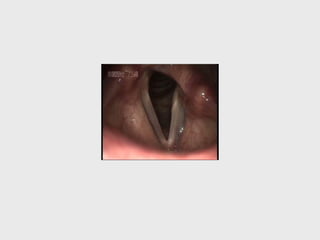

position of vocal cords

normally :

breathing -

abducted

phonation -

adducted

swallowing -

add.

THEORIES TO EXPLAIN THE POSITION

OF VOCAL CORDS IN PARALYSIS

• 2. WAGNER AND GROSSMAN 'S LAW

" cricothyroid muscle ( supplied by SLN)

which has adductor function, keeps cord in

paramedian position."

VOCAL

CORDS

PM pure

RLNP

2. POSITION OF VC : median or paramedian